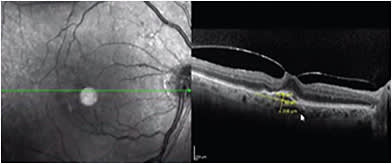

The 2 current indications for focal/grid macular laser for DME include: non-center-involving DME (Figure 2) and ETDRS-defined DME (CS-DME).5 Some retina specialists add laser to areas of focal thickening/areas of leakage; usually microaneurysms (MAs) as add-on therapy to injection, as this can decrease injection burden. However, it has not been studied on a wide scale. Others use it as a rescue therapy once central macular thickness decreases to 400 microns to get an adequate response to injections. Parameters using diode or argon laser include the smallest spot size (50-100 microns) you can obtain a minimal reaction with it (faint greyish) with minimal duration (0.05 -0.1 seconds) applied to the area outside the foveola (50-300 microns from the center). Subthreshold (micropulse) diode laser has been tried in DME to minimize collateral damage by fragmenting the laser beam into micropulses, which can also be applied to the subfoveal area in a noticeably short duration combined with a longer interval (e.g., 5% duty cycle), allowing energy to be dissipated by the choroidal flow so it’s only stimulating the RPE. No clinical trials are available to demonstrate superiority to conventional laser or anti-VEGF.6